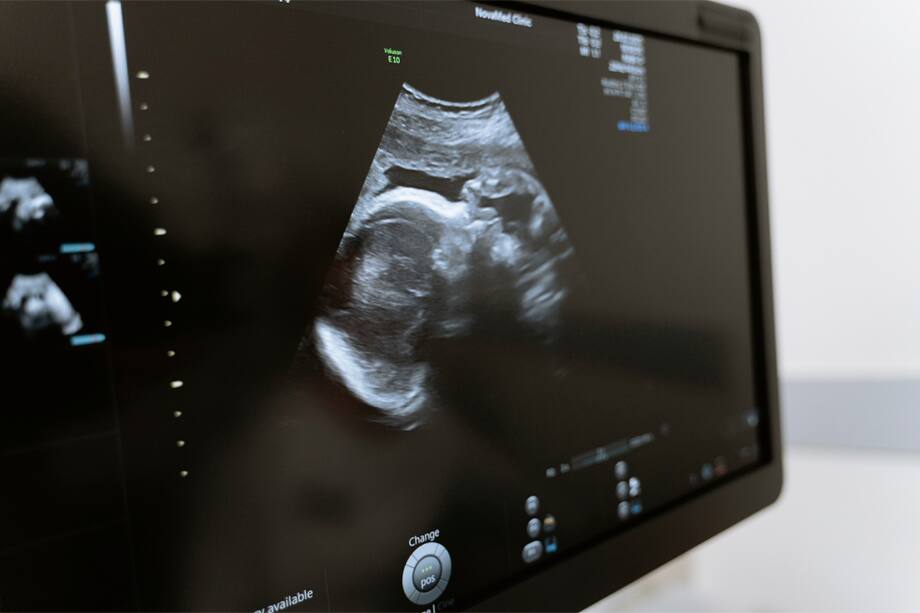

Cuando descubres que estás embarazada es importante que acudas a tu médico lo más pronto posible, para confirmar que todo esté en orden y, en especial, para revisar que no tengas un embarazo ectópico.

Tras descubrir que estás embarazada debes ir a un chequeo para descartar un embarazo ectópico ¿Qué es esta condición? Aquí te lo explicamos.